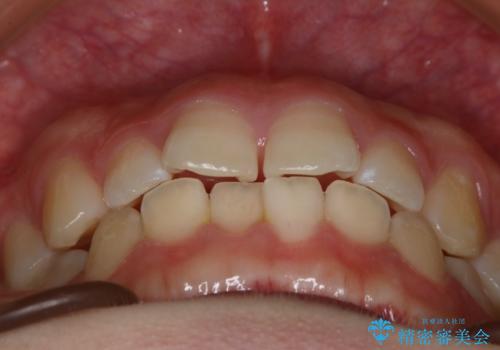

- 前歯のガタつきの改善を主訴に来院された患者様です。

ガタつきによる上顎正中の空隙や歯の突出感も気にされていました。